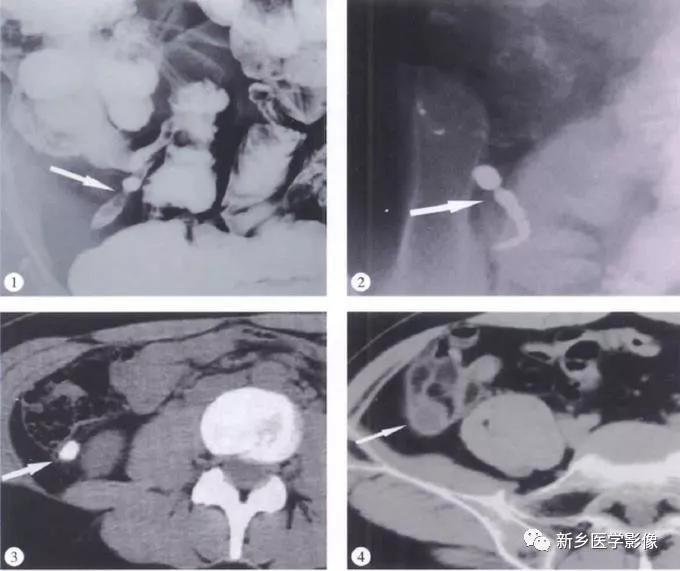

(1)BE:盲肠内侧壁光滑球形肿块压迹,末端小肠推压移位。阑尾未见钡剂充盈。

(2)右下腹卵圆形肿块,有或无钙化声影。腔内以低度回声典型。

(3)CT:盲肠尖区域薄壁囊性肿块,边界清晰,呈长圆形,与盲肠间解剖关系密切,环形钙化壁。增强壁强化,内容物无强化。腔内出现气泡/气液平伴感染。腹膜假黏液瘤典型为腹膜分叶病变,使空腔脏器移位或变形,实质器官边缘呈“扇贝”改变。

(4)MRI:右下腹囊性肿块,冠状面位髂肌和腰大肌形成“V”形间隙内,与盲肠关系密切,可位于盲肠内下方或后下方,盲肠外压改变。